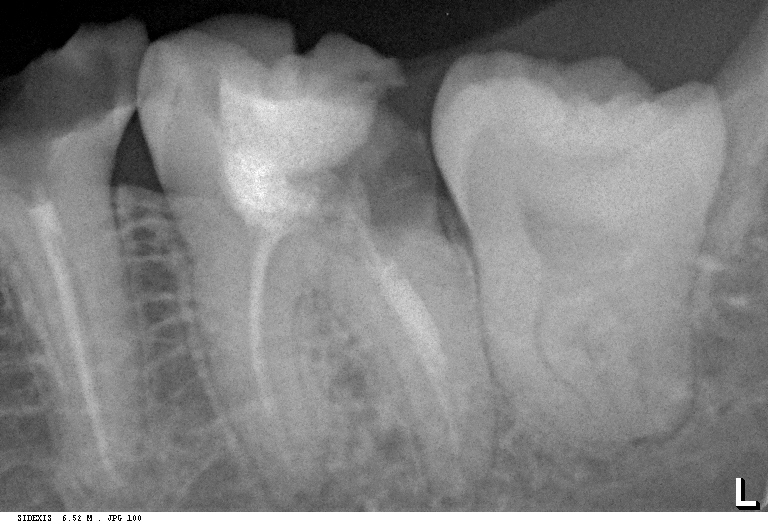

Удаление зуба мудрости на левом снимке обошлось пациенту в 4827 рублей. Удаление зуба мудрости пациенту на правом снимке обошлось пациенту в 4516 рублей, несмотря на то, что технически сделать это сложнее, а сама операция требует больше расходников и трудозатрат.

По действующему прейскуранту клиники («Канадская Стоматология») удаление данных зубов обходится немногим более 6000 рублей. Можно убедиться на стойке у администратора.